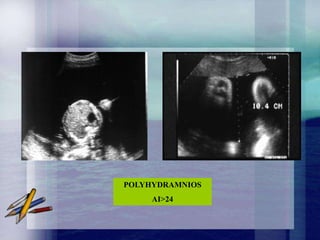

HYDRAMNIOS

Excès anormal du volume de liquide amniotique

défini en échographie par une citerne de liquide

amniotique supérieure à 8 cm ou un index

amniotique supérieur à 25 cm.

POLYHYDRAMNIOS

AI>24